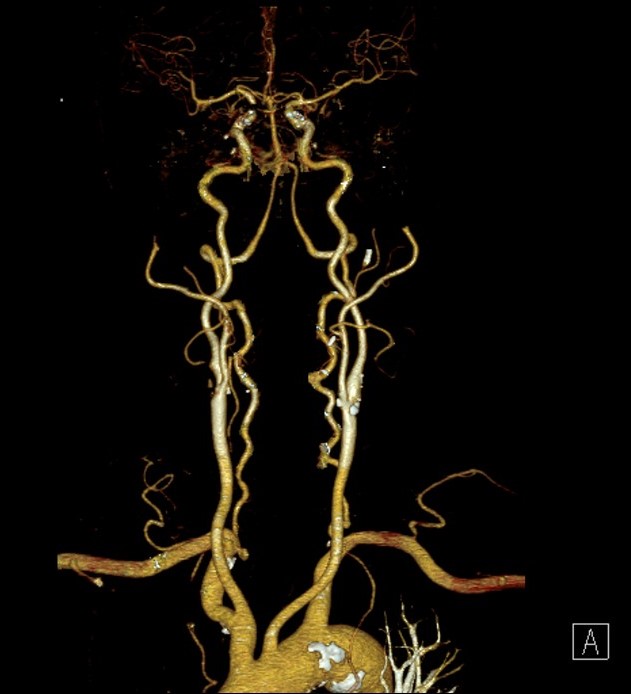

Anatomy of Carotid Artery

Image taken from Radiopaedia.org

Appearance of Carotid Artery in CT VRT Image

- VRT Radial Ranges CTA Carotid